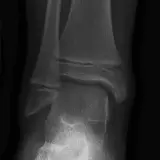

Over 2,100 interactive radiology cases, curated by radiologists for your level of training. Scroll, window, and view cases full screen — just like on PACS. Click linked findings in each writeup to jump straight to them on the image. Cases include sample reports, a focused discussion section, original illustrations, and videos.

Casos totalmente interactivos con las herramientas que esperaría de un PACS: scroll, ventana, zoom, pan, mediciones, ROI y modo de pantalla completa.

• Anotaciones enlazadas

Anotaciones extensas resaltan los hallazgos clave directamente sobre los casos. Haga clic en los hallazgos enlazados dentro de la descripción del caso para saltar a su ubicación exacta en el estudio.

Casos Interactivos

Desplace, arrastre, ajuste ventana y amplíe como en una estación PACS de trabajo

Aprenda con eficiencia gracias a hallazgos de imagen anotados e ilustraciones